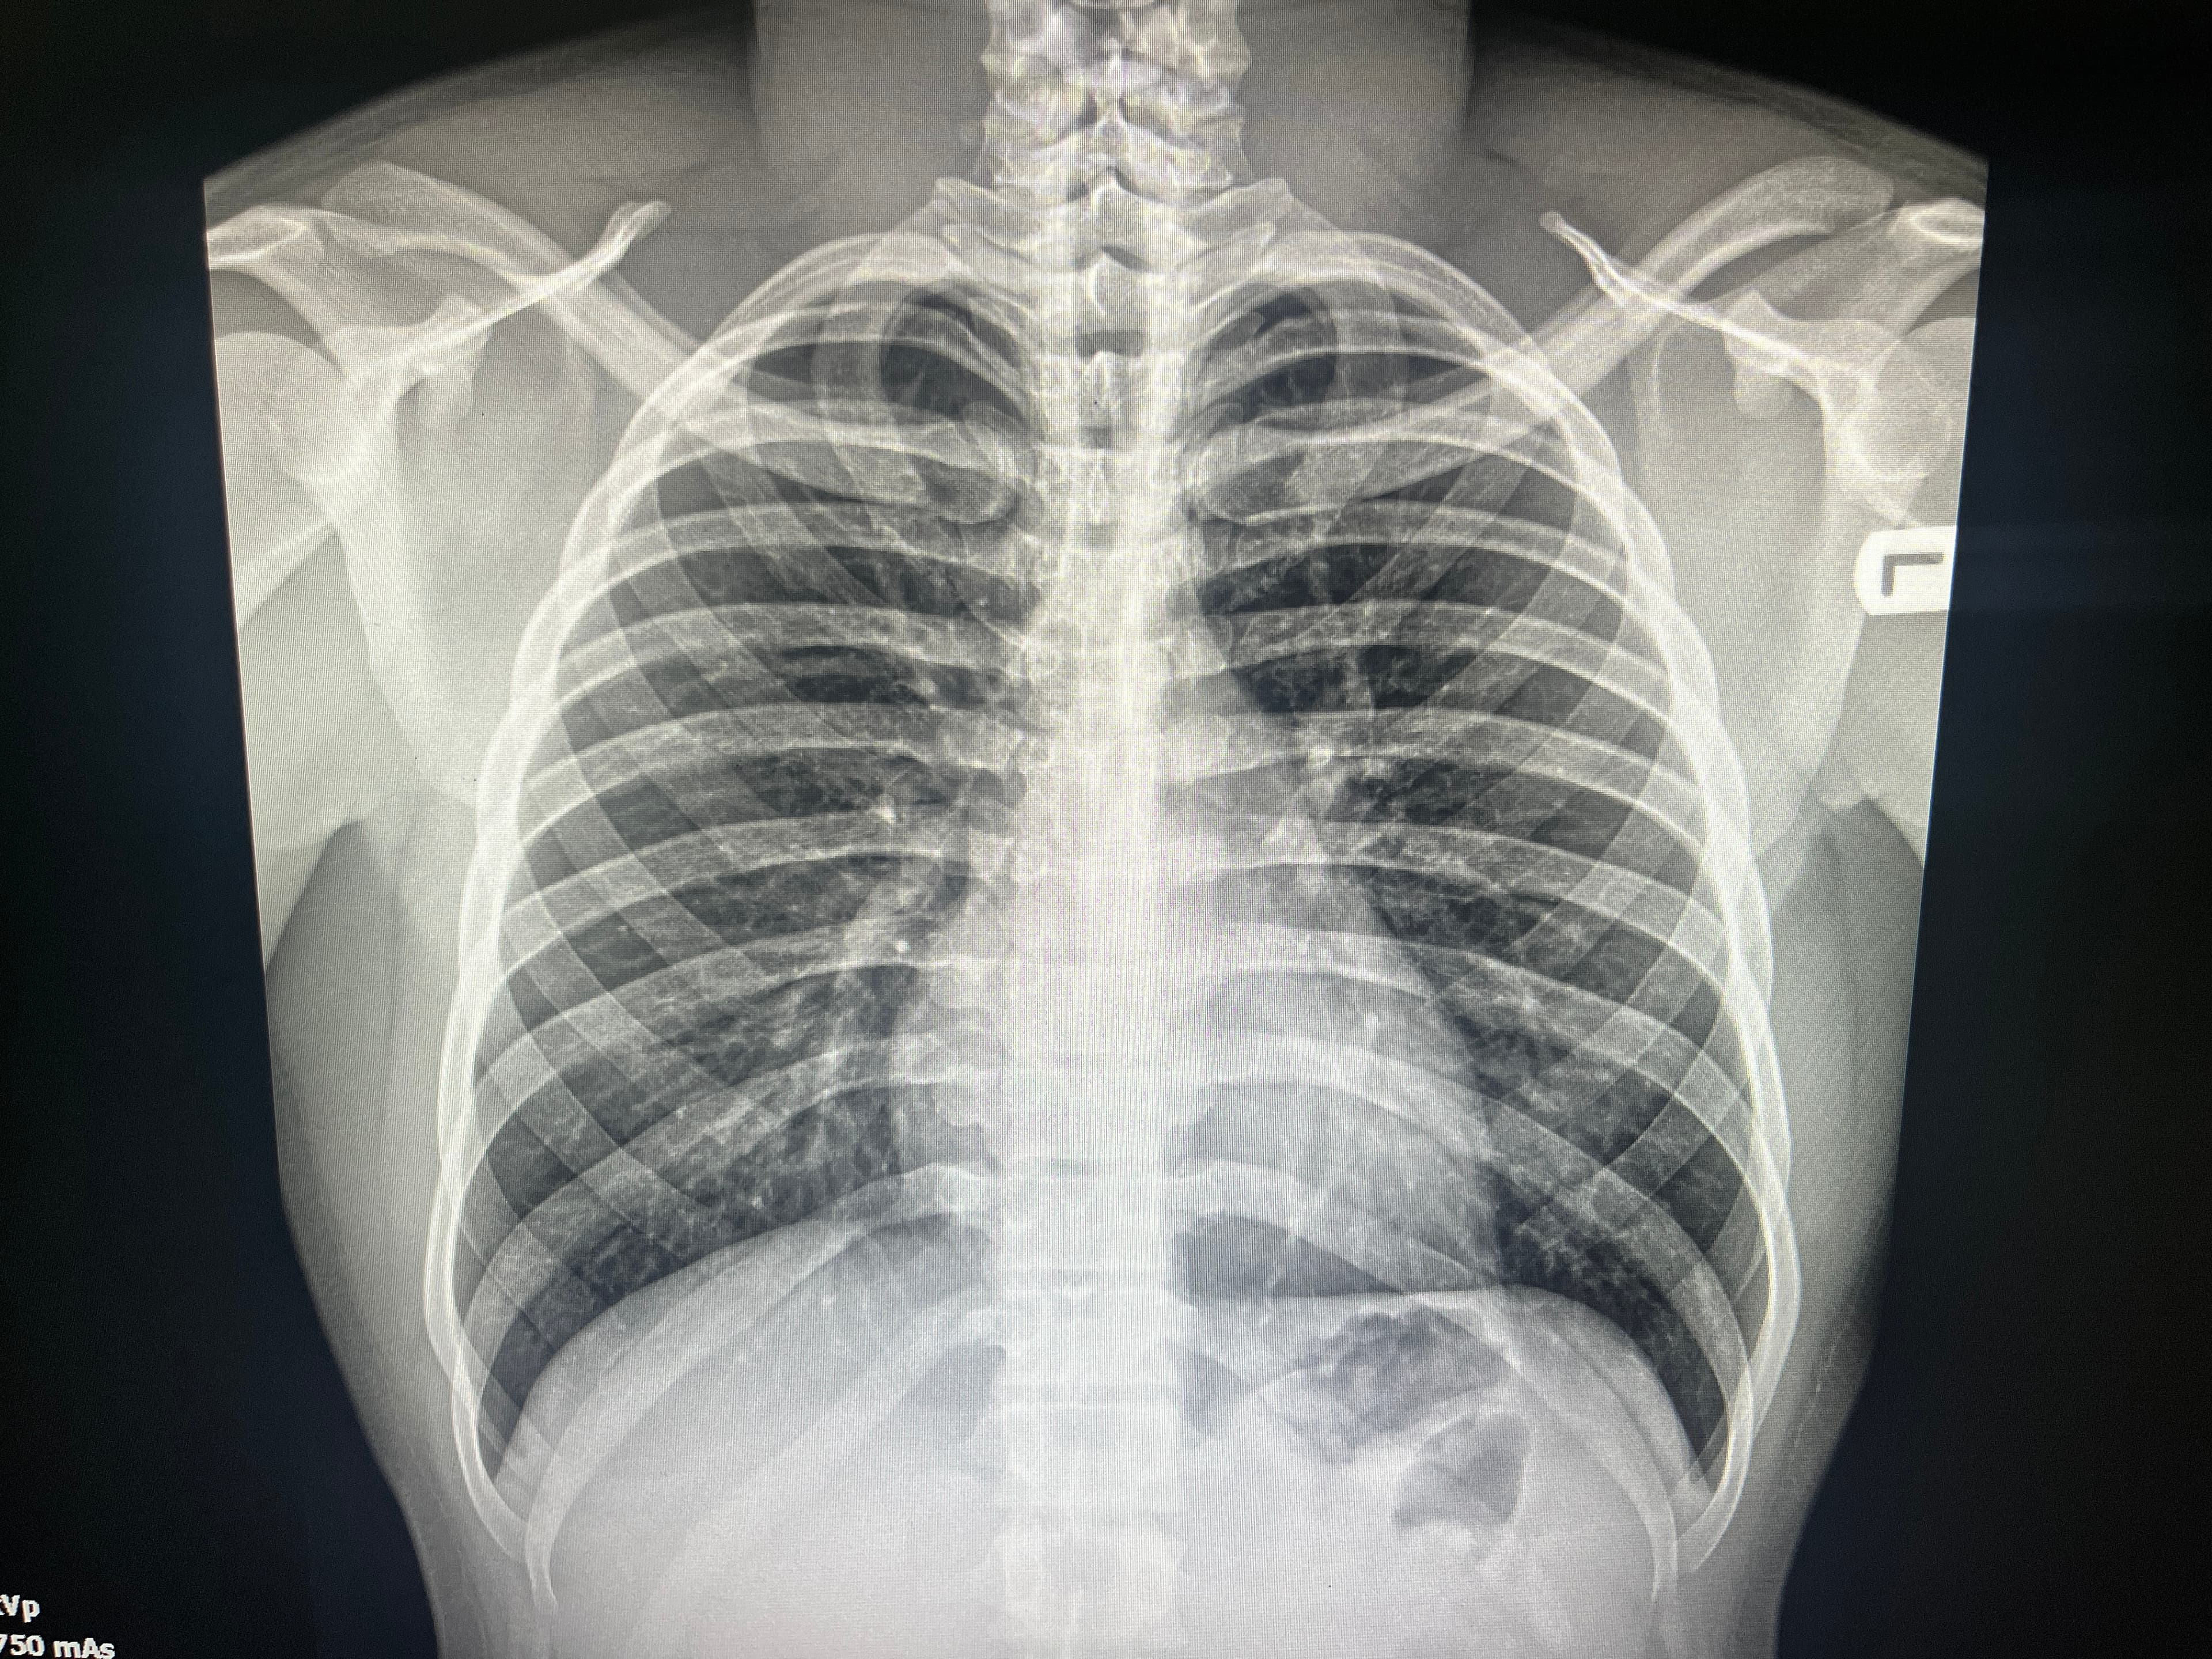

Imagem 1, anatomia do problema

![Raio X de tórax para ilustração de tarefas de localização]

A localização anatômica em radiografias de tórax é um gargalo clássico quando se tenta gerar relatórios estruturados. O salto de IoU reportado sugere que já é possível iniciar pilotos de marcação automática com revisão, reduzindo tempo de anotação e padronizando achados em pipelines de QA.